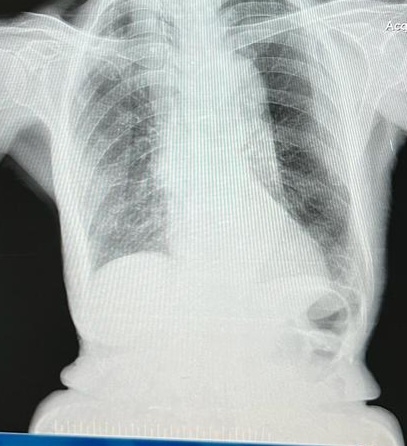

CHEST X RAY